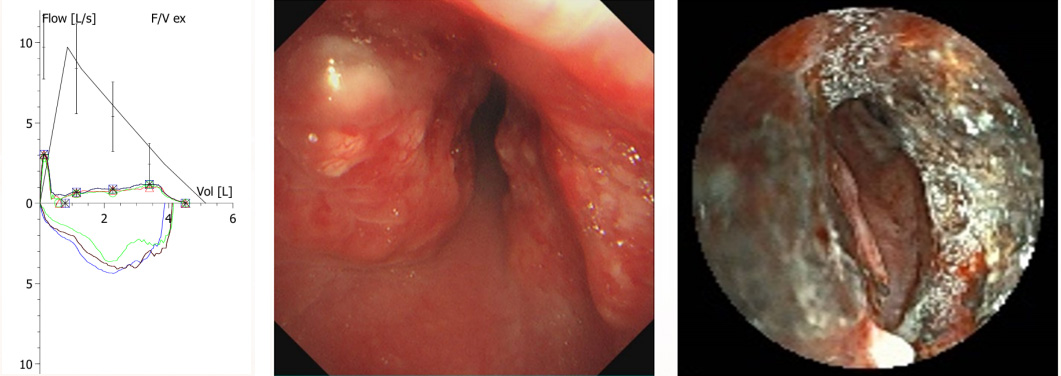

【肺功能检查】

患者表现为极重度阻塞性肺通气功能障碍,F-V曲线显示呼吸双相流量下降,符合固定型大气道阻塞特征。

【支气管镜检】

气管中下段新生物,管腔重度狭窄,触之易出血,已进行支气管镜内镜治疗。